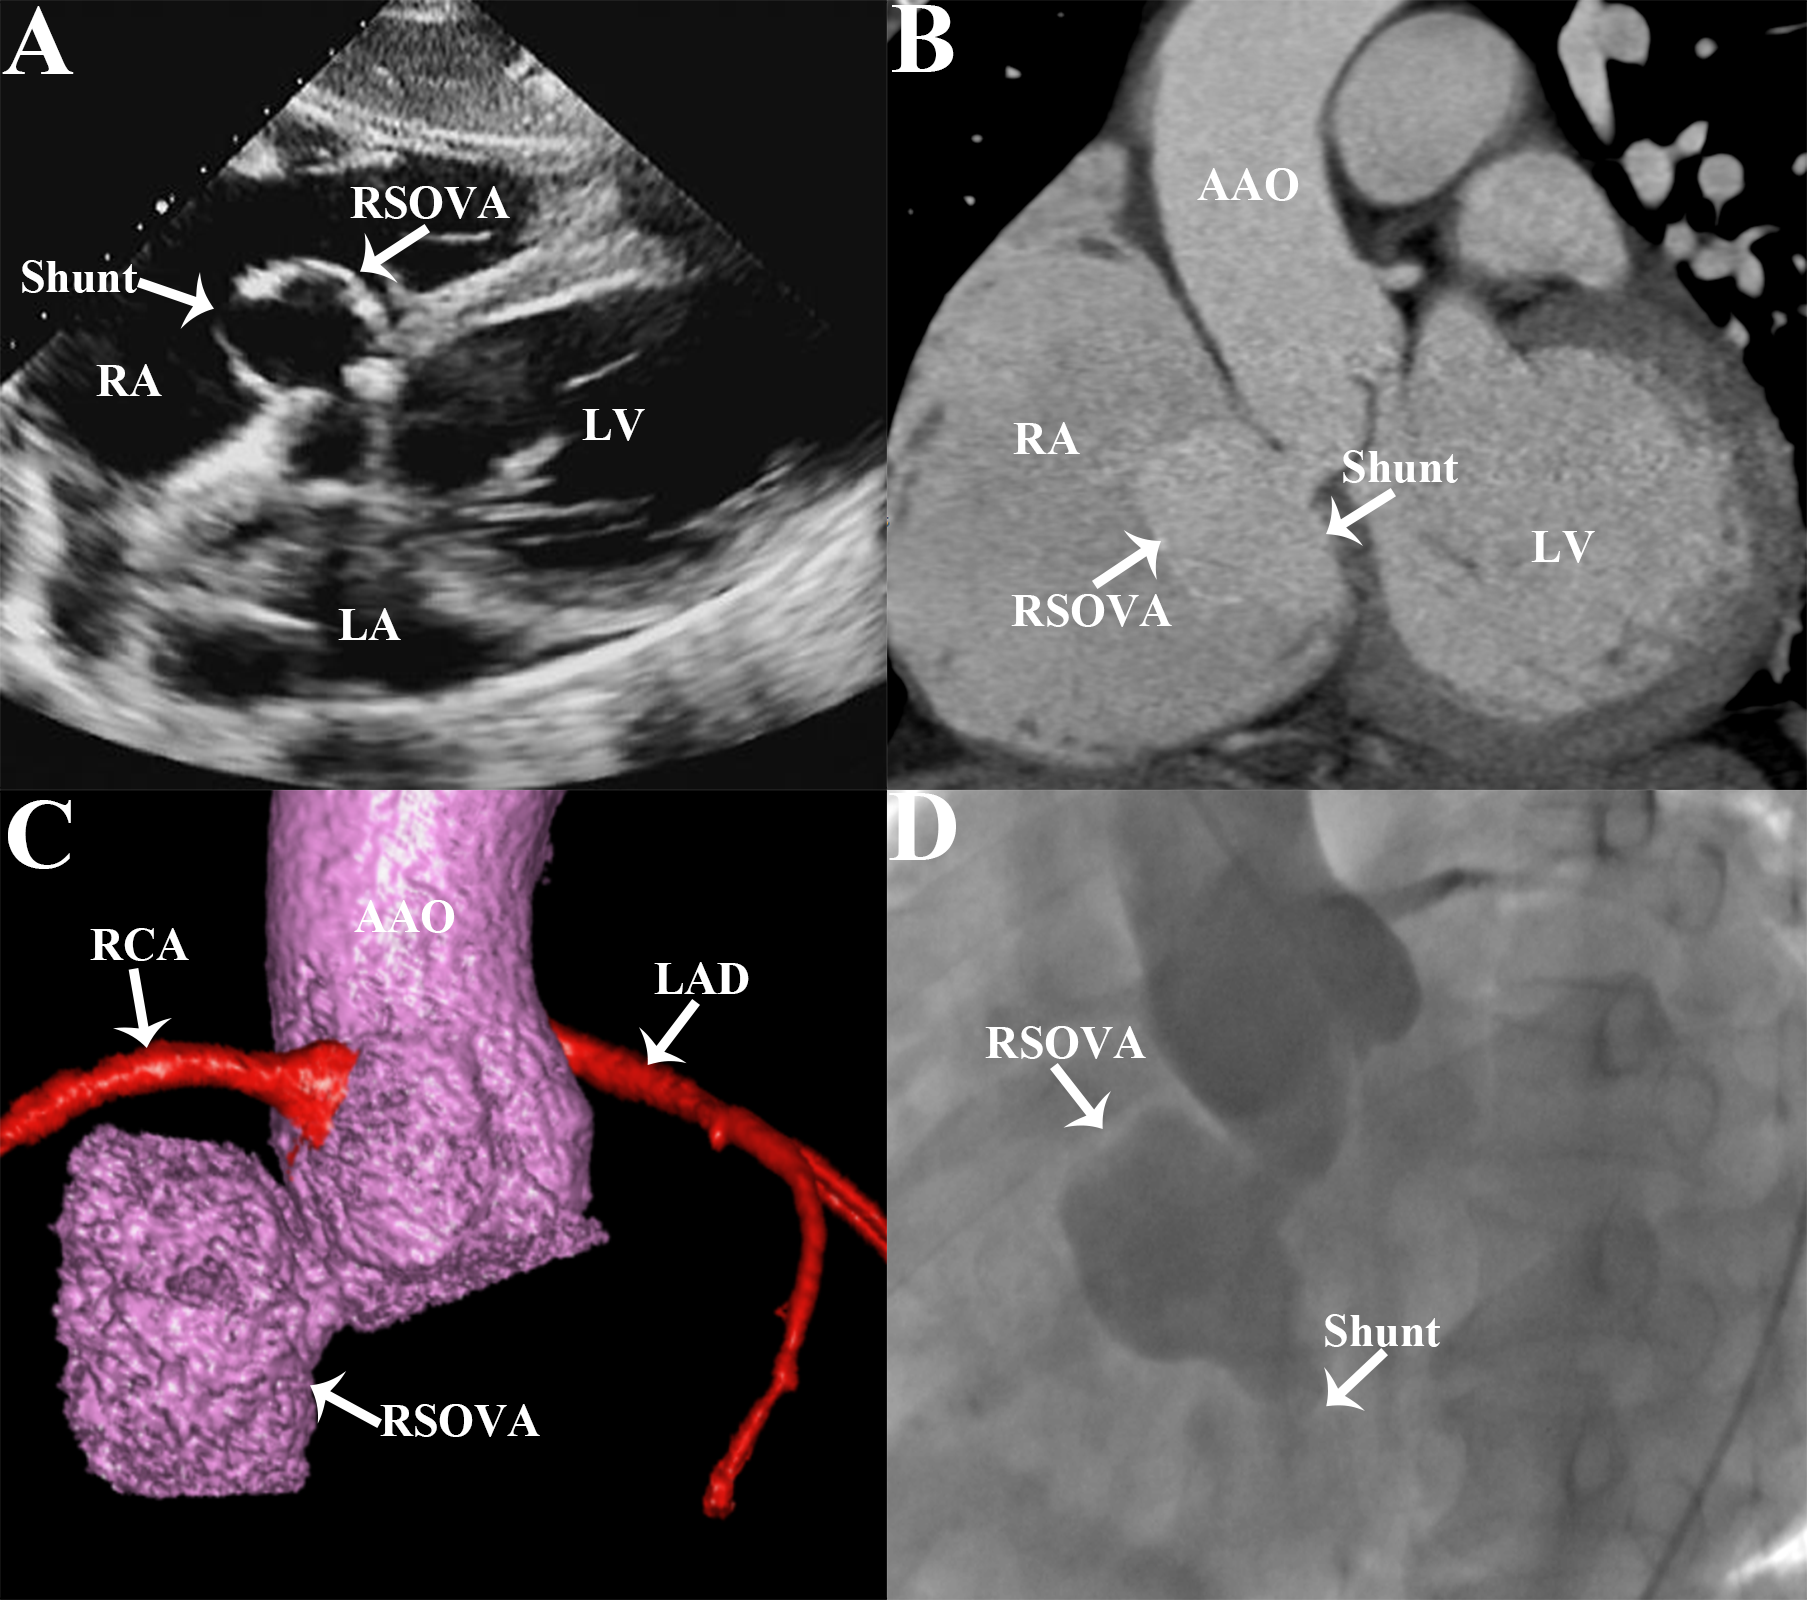

A 50-year-old man presented with chest tightness and shortness of breath after activity for 1 month. Cardiac auscultation revealed a continuous murmur in the fourth intercostal space at the right edge of the sternum. Electrocardiogram showed atrial fibrillation and delayed intraventricular conduction. Transthoracic echocardiography revealed a 32 x 31-mm sinus of Valsalva aneurysm (SOVA) arising from the non-coronary sinus that had ruptured into the right atrium (RA), leading to the formation of an aorto-right atrial shunt (Figure A), with associated mild to moderate aortic valvar regurgitation and mild mitral valve insufficiency. Cardiac computed tomographic angiography (CTA) showed the non-coronary SOVA ruptured into the RA (Figure B and C). Aortic root angiography confirmed a non-coronary SOVA rupturing into the RA with a diameter of approximately 12 mm (Figure D, Video 1).